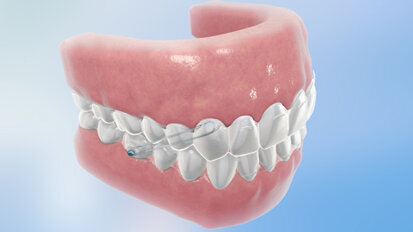

L'orthodontie sans attaches fixes

En conformité avec l'esthétique de plus en plus sophistiquée, pour le patient qui doit subir un traitement orthodontique avec des ...